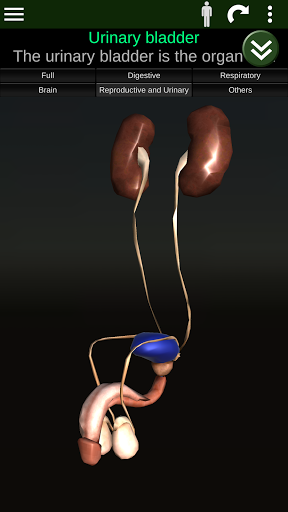

Internal Organs in 3D Anatomy لـ Vodafone Smart N9 Lite

(الأجهزة الداخلية في)

Internal Organs 3D Anatomy 3.4